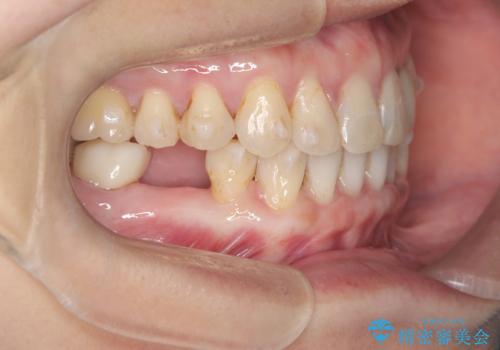

- 歯と歯の間に大きなスペースがある「空隙歯列(すきっ歯)」と、一部の歯が欠損していることによる噛み合わせの不安定さを主訴にご来院されました。

精密検査の結果、全体の隙間を閉じるだけでは適切な咬合バランスが得られないため、まずはインビザラインを用いて歯の位置を理想的な場所へと整える計画を立案しました。矯正によって欠損部位に適切なスペースを確保した後、その部分にインプラントを埋入することで、審美性と機能性の両立を目指しました。